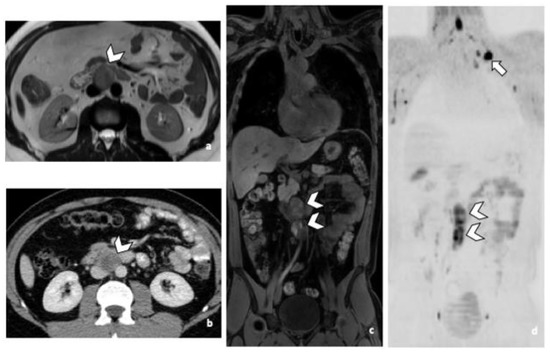

Figure 4.

Comparison of WB sequences in a 39-year-old patient with NSGCC. Axial T2-weighted (a), 3D T1 GRE In Phase (b) and high b-value DWI (b = 1000 s/mm2) MR images. One of the readers missed an enlarged paraoesophageal lymph node (arrowhead) demonstrating a high signal intensity in T2 (a), barely visible in T1 and presenting a restricted Diffusion (c). Abbreviations: NSGCC: Non-Seminomatous Germ Cell Cancer, 3D: Three Dimensional, T1 GRE: T1 Gradient Echo, DWI: Diffusion Weighted Imaging.